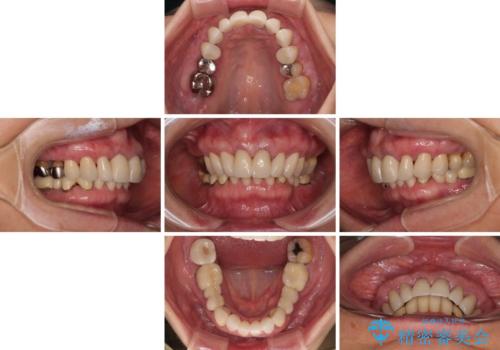

- 歯肉ラインの段差や、歯根が黒く見えている前歯を気にして来院された患者様です。

海外に在住で、年に2度ほど帰国するタイミングで治療を行いたいとのことでした。

前歯のインプラントは埋入されたポジションが望ましい位置ではなく、インプラントを活用して段差を回収することは不可能と判断し、歯肉移植によりインプラントを隠して、ブリッジにて歯肉ラインを整えることとしました。

臼歯部の治療も必要と判断されましたが、前歯部を中心とした審美領域をオールセラミッククラウンによる補綴治療を行うこととしました。

帰国時のみの治療であったため、治療期間は長くなりましたが、最小限の来院回数で、気になっていた前歯をきれいに整えることができました。